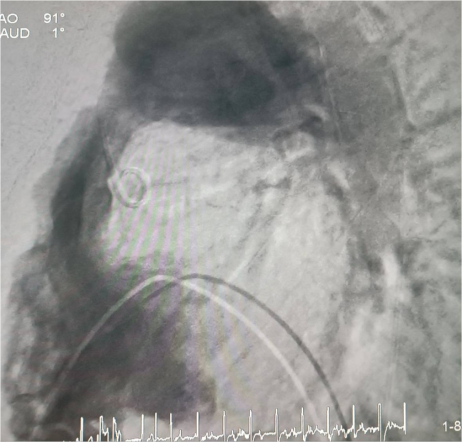

У пациента из Луганской Народной Республики просвет ранее имплантированного кондуита составлял 1,5 сантиметра, поэтому рентгенхирурги на первом этапе расширили его методом баллонной дилатации. При этом был риск разрыва сосуда, поэтому, чтобы избежать возможных осложнений, медики сначала имплантировали стентграфт – металлический каркас, покрытый герметичным полимером. Просвет кондуита удалось расширить до необходимого диаметра. Затем через бедренную вену хирурги доставили к сердцу искусственный биологический клапан лёгочной артерии Myval индийского производства.

Сложную операцию провела команда врачей Педиатрического университета - рентгенэндоваскулярные хирурги Михаил Комиссаров, Владимир Приворотский и Иван Алешин. Неоценимую помощь медикам СПбГПМУ оказал заведующий отделением рентгенэндоваскулярных методов диагностики и лечения  Городской многопрофильной больницы №2 Евгений Шлойдо.